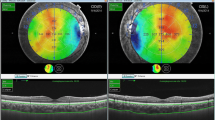

The SCT and CT values in each macular subfield of the ETDRS grid by main group are shown in Table 2. The coefficient of variation between the two observers in the manual SCT measurements was less than 4%. Manual correction on the 12 mm radial B-scan cases was needed in 70% of cases for the inner margin of the choroidal junction. The mean SCT was significantly higher in the KG than in the CG (357 ± 63 μm vs. 325 ± 57 μm, p = 0.01). The mean CT was significantly greater in the KG than in the CG in the central ring (331 ± 56 μm vs. 300 ± 53 μm, p = 0.006) and in seven parafoveal sectors of the ETDRS grid (all macular areas, p < 0.05), except in the outer nasal ring (KG, 223 ± 55 μm vs. CG, 237 ± 51 μm, p = 0.197). The topographic maps of both types of patients are shown in Fig. 2. The differences between both groups per each parafoveal sector are illustrated in Table 3. In the subfoveal area (SCT, cCT), there was a similar difference between groups (32 and 31 μm, respectively), whereas the nasal macular zone increased to a lesser extent in the inner (24 μm, 8.66%) and outer ring (14 μm, 6.30%) than in the temporal, superior, and inferior macular areas.

Early Treatment Diabetic Retinopathy Study (ETDRS) topographic map in a healthy subject (A) and in a grade 2 keratoconus (KC) patient (B) with its corresponding B-scan (bottom). The dashed white line, represented in the lower B-scan, shows the choroidal difference (white arrow) between both subjects. Significant choroidal thickening was observed in KC eyes in eight out of nine macular sectors of the ETDRS grid, except in the outer ring of the nasal area